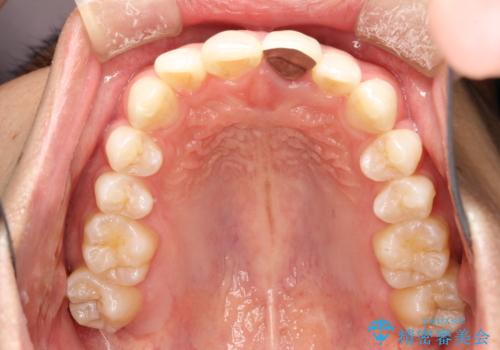

インビザラインによる矯正治療(非抜歯) 下の前歯の歯並びの改善

- 主に下の歯並びの改善を主訴としてご来院されました。

右下の犬歯と前歯が大幅に重なっているのと、歯の向きも大きく横に倒れています。この部位の正常な配列のためには、3次元的に大幅な移動が必要となりました。

インビザラインの特色を生かした歯牙移動計画を作成し、非抜歯にて治療を行いました。